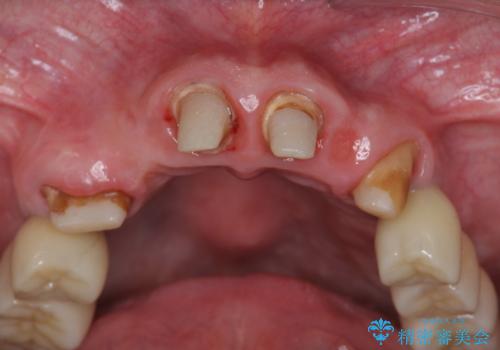

多発した虫歯による咬合崩壊 インプラントを用いた全顎治療

- 「これまで歯の治療をおざなりにしてしまい本当に後悔している。 時間と費用がかかってもいいので、しっかりと安心してかめるような状態にしてほしい。」、と全体的な治療を希望され来院されました。

歯の破折・再発した大きな虫歯・根尖病変・歯の欠損、これらの問題を根管治療・歯周外科・インプラント治療・セラミック補綴を行うことで一つづつ解決し安定した咬合状となるよう治療を進めます。